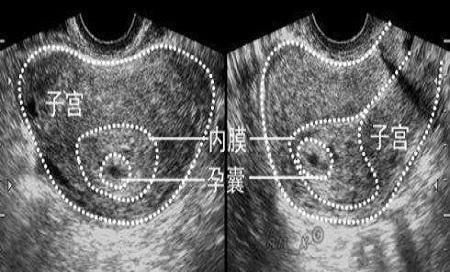

首先来说一下什么是孕囊?孕囊只有在孕早期可以看得到,是在怀孕40天左右形成的,也是最初的怀孕形态。

当受精卵植入到子宫内膜后,就会逐渐成长为孕囊,是被羊膜、血管网等包裹起来的小胚胎,有胚胎组织。

孕妈不放心的话,可以通过B超在宫腔内看到孕囊,随着胚胎不断成长,孕囊内会形成胎芽、胎心,如果孕妈在医院检查时,看得到孕囊,胎心和胎芽,就可以确认为宫内妊娠。

孕囊的特点:孕妈自己不会看拍出来的片子,可以对照下面的几项孕囊特点来看一下:

孕囊正常的特点:

- 孕囊的位置可以位于子宫的上部、中部、宫底,也可以位于前壁和后壁,都是属于正常形态,孕妈不必太担心;

- 孕囊的形状为圆形和椭圆形,看上去清晰可见,就是正常的;

- 月经期比较规律的女性,停经35天之后,就可以在宫腔内看到孕囊。

- 在怀孕6周时孕囊直径约2厘米,怀孕10周时约5厘米。

如果在B超时,看到的孕囊很不清晰,也呈现不规则状态,位置靠近下方,而且孕妈伴有YD流血或者肚子很痛的话,可能是要发生流产现象。